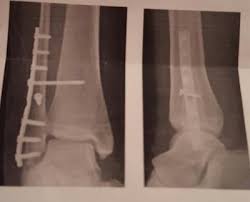

Weber-c-fraktur. Use the information below to gain a better understanding of your injury and what can be done to maximise your recovery. Komplizierte Sprunggelenkfraktur des Fußes mit Syndesmosenbeteiligung Die Einteilung der Frakturen A-C erfolgt nach dem Chirurg Wilhelm Weber 1872-1928. It has a role in determining treatment.

Fraktur oberhalb der verletzen Syndesmose Membrana interossea häufig auch rupturiert Die Maisonneuve-Fraktur wird als Sonderform der Sprunggelenksfraktur auch als Weber C klassifiziert. This normally takes approximately 6 weeks to heal. Die Weber-Klassifikation eine Methode zur Beschreibung von Sprunggelenksfrakturen.

Weber C Fraktur. Neben der Weber C Fraktur gibt es auch noch die Fraktur der Klasse A und B. Was ist eine Weber-C-Fraktur. DayZ sa well kit DayZ Expansion Building Kits - YouTub. Verschobenem Bruch dislozierte Fraktur undoder. It has a role in determining treatment. Weber C Fraktur. Look up the French to German translation of weber c fraktur in the PONS online dictionary. The Weber ankle fracture classification or Danis-Weber classification is a simple system for classification of lateral malleolar fractures relating to the level of the fracture in relation to the ankle joint specifically the distal tibiofibular syndesmosis.